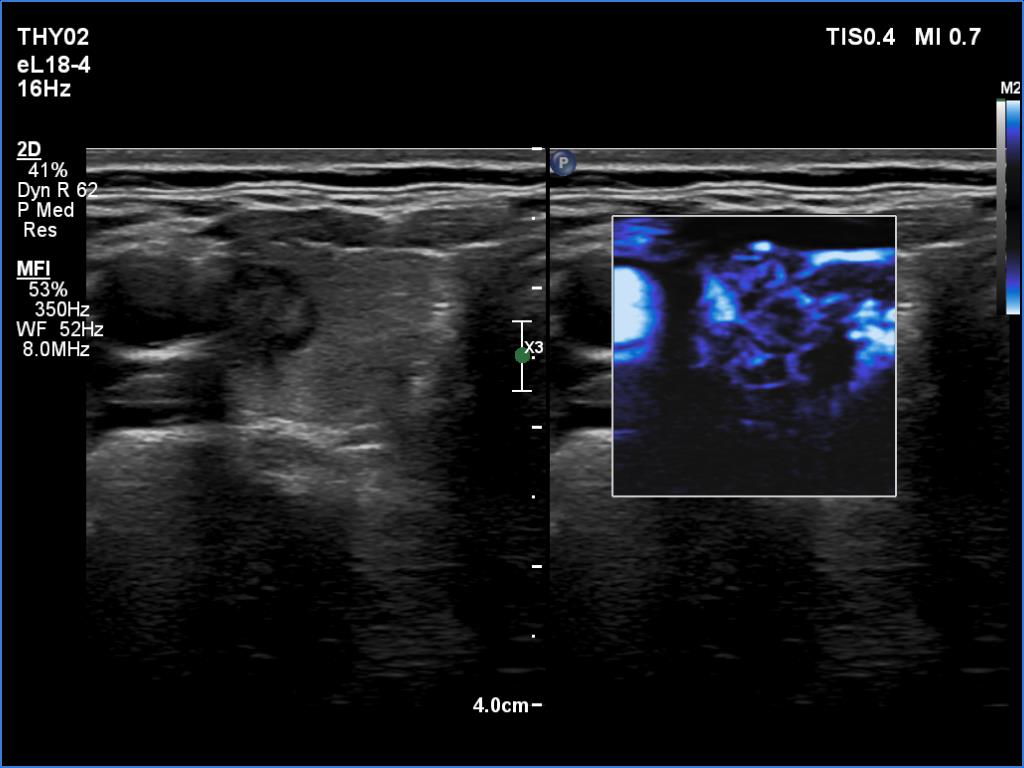

First examianation (first row of images):

Clinical data: A 43-year-old woman was referred for an evaluation of a thyroid nodule detected on screening.

Palpation: a not firm nodule in the right lobe.

Laboratory examination: TSH 2.05 mIU/L.

Ultrasonography. The thyroid was echonormal. There was a nodule in the ventrolateral part of the right lobe. The lesion was composed partly of hypoechogenic, partly of echonormal areas. There was one echogenic punctate focus within. The microflow imaging revealed increased intranodular blood flow. The ventral part of the lesion was hard on elastography.

Cytological diagnosis: papillary carcinoma.

A right lobectomy was performed. Histology revealed a T1a papillary carcinoma.